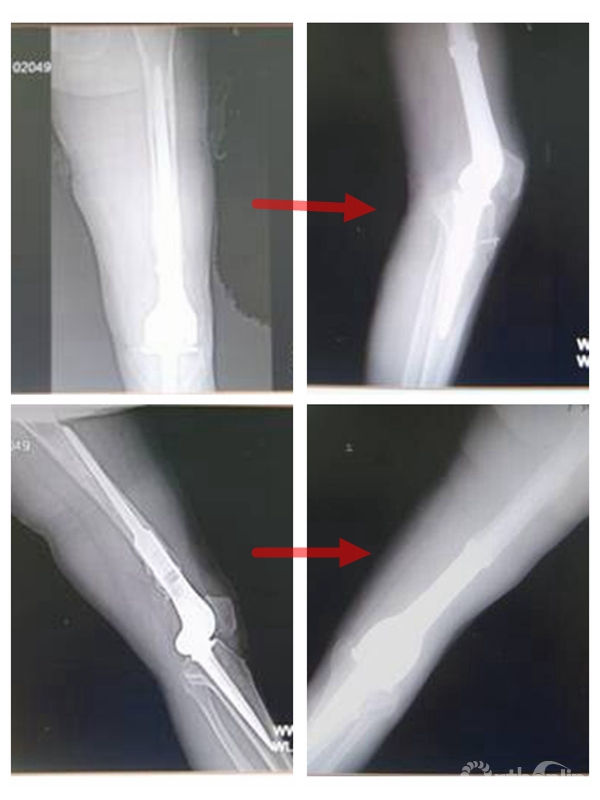

肿瘤型人工膝关节翻修技术

2007年广东省骨科矫形技术与植入材料重点实验室成立,下设数字骨科研究室,对复杂骨科手术进行了计算机辅助观测和个性化术前规划,指导手术;进行了复杂骨盆骨折、小儿骨盆肿瘤、肘关节内翻畸形、先天性半椎畸形脊柱侧弯、髋关节发育不良虚拟手术与快速成形辅助手术; 开展了髋、膝肿瘤个性化设计,CDM定制,肿瘤假体置换、翻修等保肢手术。